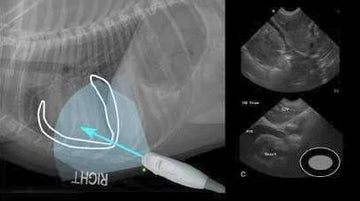

El monitoreo del corazón en animales mediante ecocardiografía es fundamental para garantizar su bienestar. La imagen ecocardiográfica que presentamos, obtenida con un equipo VINNO VET, muestra cómo las tecnologías avanzadas de ultrasonido permiten realizar estudios cardíacos detallados. Este método no invasivo proporciona información precisa sobre la anatomía y función cardíaca, mejorando significativamente el diagnóstico de enfermedades cardiovasculares en mascotas y animales de mayor tamaño.

- El equipo VINNO VET utilizado en esta ecocardiografía ofrece alta resolución y velocidad de procesamiento, lo que permite a los veterinarios obtener imágenes claras y detalladas, cruciales para realizar diagnósticos precisos. Además, la interfaz amigable facilita su uso en clínicas veterinarias y hospitales, permitiendo ajustes rápidos durante la evaluación de animales de diversas especies.